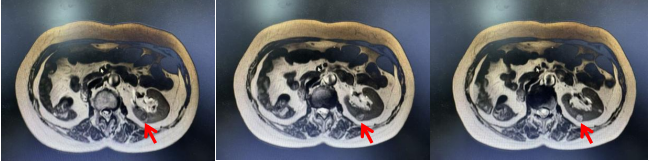

该患者因对侧肾脏已切除,仅存一侧肾脏承担全部代谢功能。此次检查发现,肿瘤位于肾中极,位置深、外突不明显,且血供丰富,给手术带来极大挑战。术中若操作稍有偏差,就可能导致肾功能丧失,患者需终身依赖透析,严重影响生活质量。面对这一复杂情况,王子琦教授、王宏磊副教授、宋洪戬医师团队多次开展病例讨论,为患者制定机器人辅助腹腔镜手术方案,兼顾肿瘤根治与肾功能保护。

术中,团队在机器人高清晰三维视野及术中超声帮助下,精准定位肿瘤边界、阻断肿瘤供血动脉,热缺血时间严格控制在20分钟以内。同时,通过术中肾脏低温保护技术,有效降低肾脏代谢需求,延缓缺血损伤,为术后肾功能恢复创造条件。在有限时间内,团队默契配合,精准完成肿瘤完整切除、创面精细缝合及集合系统重建,手术过程流畅、精准,出血量极少。

治疗前不同横截面影像